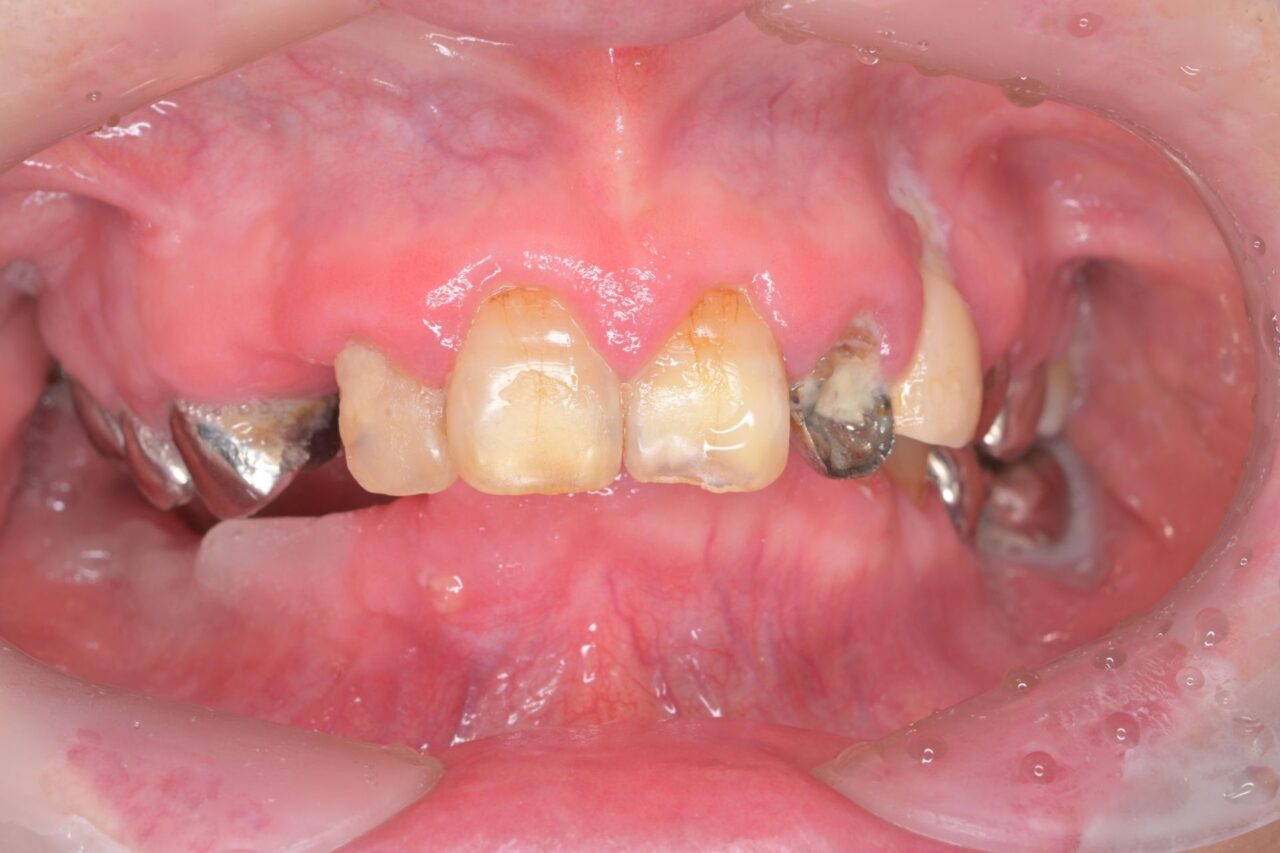

初診時の状態

正面

下の歯が全く見えません。

奥歯が無くなって噛み込みが深くなってしまい、下の前歯が上の歯茎に刺さっている状況です。